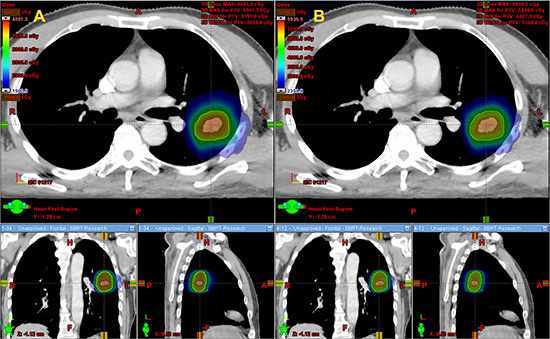

Dose comparison between the 1 × 34 Gy and 4 × 12 Gy dose schedule

Dose to the GTV, PTV-GTV (PTV minus GTV), lung and chest wall (CW) between the two dose schedules after conversion to biologically equivalent dose in 2 Gy fractions (EQD2) were listed in Table 2. All the dose comparisons were statistically significant with p-values < 0.05. Specifically, the 1 × 34 Gy schedule provided up to 47.1% and 44.1% higher dose on average for the GTV and PTV-GTV, respectively. Moreover, the 1 × 34 Gy schedule also added 3.1–7.9% more dose on average to V10–V60 of the CW. However, the dose delivered to the lung was much smaller, with V5–V70 increasing by 1.0–2.2%. The cumulative dose volume histogram (cDVH) of the GTV, PTV-GTV, lung and CW after EQD2 dose conversion is presented in Figure 1. Dose distributions from the transversal, coronal and sagittal views are presented in Figure 2.

Figure 2: Dose distribution from the transversal, coronal and sagittal views between the two dose schedules. The dose color wash slider was set at 15 Gy for the 1 × 34 Gy schedule and 23.59 Gy for the 4 × 12 Gy schedule (the same EQD2 dose). (A) Dose distribution of the 1 × 34 Gy schedule. (B) Dose distribution of the 4 × 12 Gy schedule.

For clarification, all doses mentioned in the article were converted to the EQD2 dose using the LQ model. The target was divided into two substructures of GTV and PTV-GTV for comparison. For GTV and PTV-GTV, the evaluating parameter was the mean dose. For the lung and CW, the analysis included the mean dose and a set of dose volume histogram (DVH)-based values. cDVH for the target and OARs were reconstructed from the individual DVH. These histograms were obtained by averaging the corresponding volumes for each dose bin of 0.05 Gy. Dose distributions from the transversal, coronal and sagittal views between the two dose schedules were acquired at 15 Gy and 23.59 Gy (with the same EQD2 dose) for the 1 × 34 Gy and 4 × 12 Gy schedules, respectively.